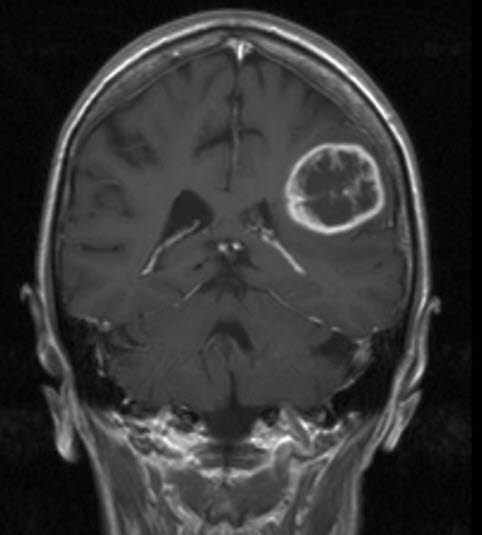

Glioblastom, koronalt snitt

Glioblastom WHO grad IV

Gjengitt med tillatelse av Radiologisk avdeling, Universitetssykehuset Nord-Norge